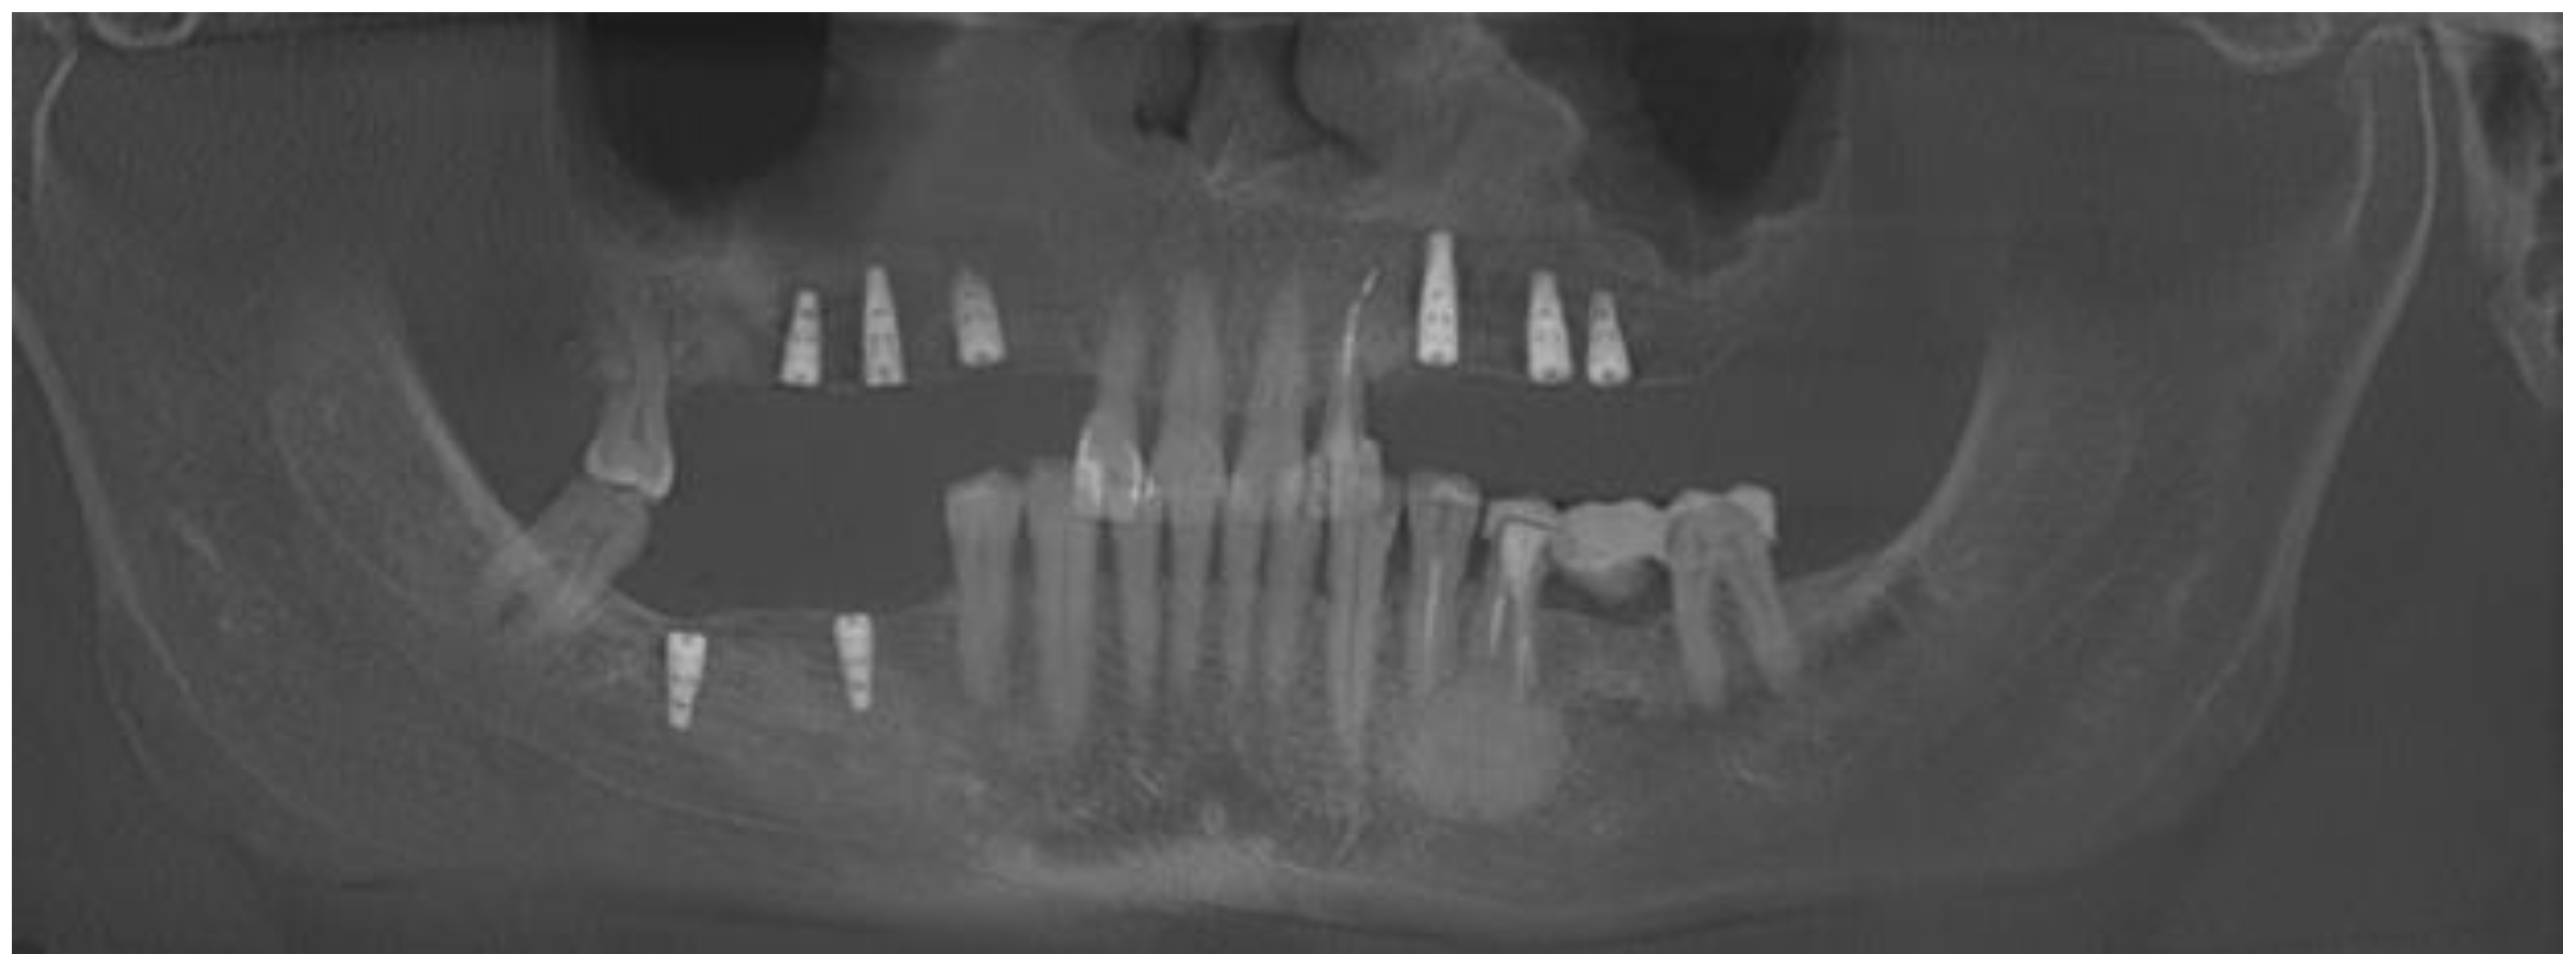

2. Case Description

- A close CBCT evaluation before surgery;